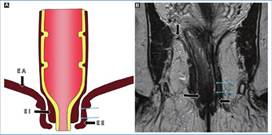

En sentido caudal, debemos identificar la unión ano-rectal y el margen anal, para de esa forma identificar el canal anal. Esta unión ano-rectal se encuentra en íntima relación con el anillo puborrectal y la porción proximal del esfínter anal externo, para identificar esta se toma como punto de referencia una línea imaginaria que une la cara inferior del pubis y el sacro3 (Fig. 5).

Otra estructura que el radiólogo debe reconocer es el esfínter anal. Este está compuesto por una capa interna, el esfínter anal interno, que es continuación de la capa muscular interna del recto; rodeado por una capa externa de músculo estriado, el esfínter anal externo, el cual se encuentra en relación con los músculos elevadores del ano y del anillo puborrectal. Ambas capas se encuentran separadas por un espacio de tejido adiposo de grosor variable: el espacio interesfin teriano7 (Fig. 6).